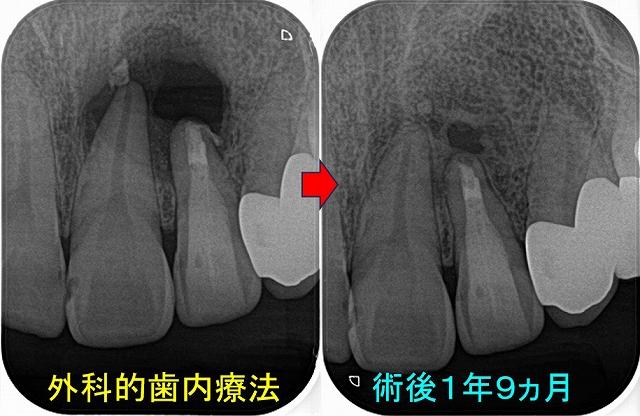

レントゲンを撮ると

はっきり根尖病変写っているんですけど・・・

過去に抜髄をしているようですが、4根管中1根(口蓋根)しか治療していない感じ

治療は2回で仕上げました。

病変の原因と思われる、MB,MB2もガッタパーチャー使用

そこから、1年後

病変は殆ど無くなってきています